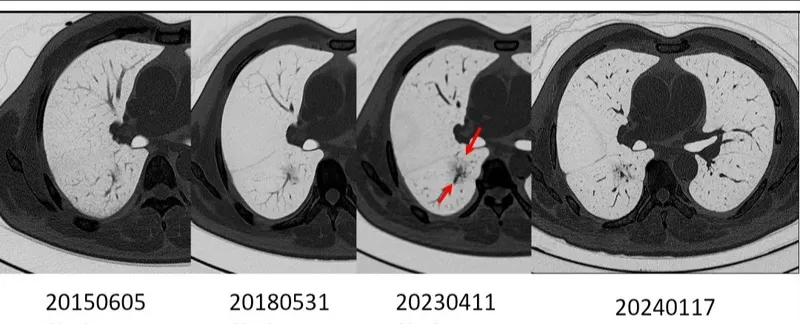

一顆結節的靜默旅程:身體與時間的對話

...顯示更多